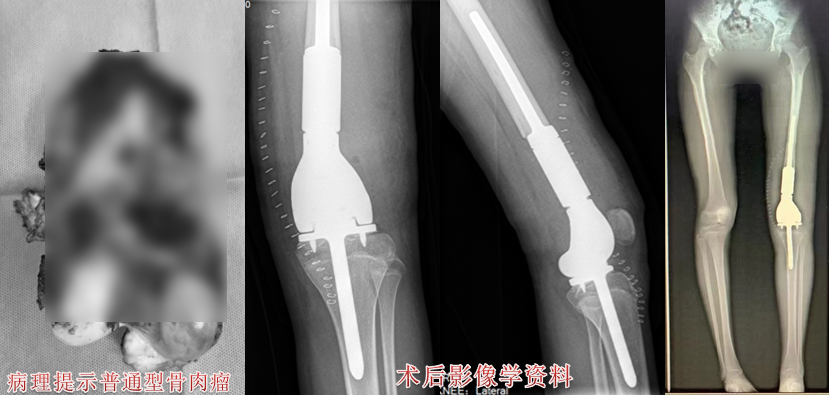

病例一

患者为一名14岁女孩,经检查,发现左股骨下段有肿物,时间长达6个多月,被诊断为普通型骨肉瘤。

2.png

在医院骨科骨肉瘤组长王新家主任医师的带领下,王伟东副主任医师及MDT团队成员充分讨论,通过制定详细的诊疗方案、对患者进行术前新辅助化疗、定制个性化假体置换、实现保留胫骨侧骨骺的保肢治疗术,术后患者恢复良好。